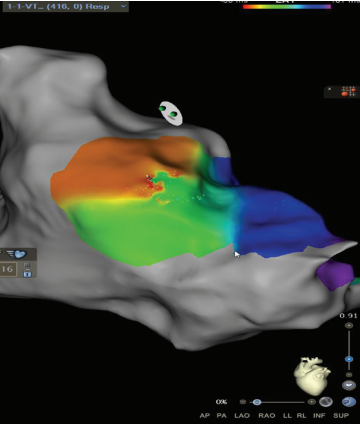

Wavefront Discontinuity Lines

The RV pacing map set was again used in a local activation time format to evaluate wavefront discontinuity lines (WADL). This recently described method of functional mapping developed by Maher et al6 uses the mapping system to automatically identify areas of slow activation and fixed lines of block to target for ablation. To visualize the lines of discontinuity, we titrated the early-meets-late setting between 25% to 35% of the mapped cycle length in the ventricle. This is visualized in Figure 3 by a white line in the same area of RVOT with activation meeting a line of block within the surgical scar emphasized by the black arrows. The WADL in this map again correlated with the same area marked as a SCAI and ILAM deceleration zone. To the author’s knowledge, there are no prior published reports of using WADL mapping in repaired TOF.